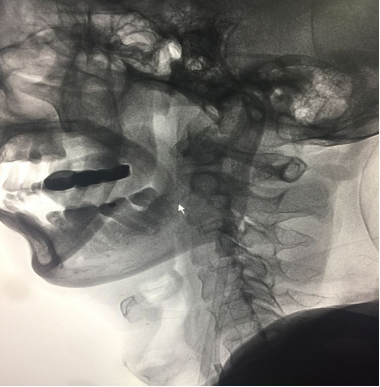

应用中间导管直接抽吸颈内动脉岩骨段

海绵窦以下颈内动脉打通